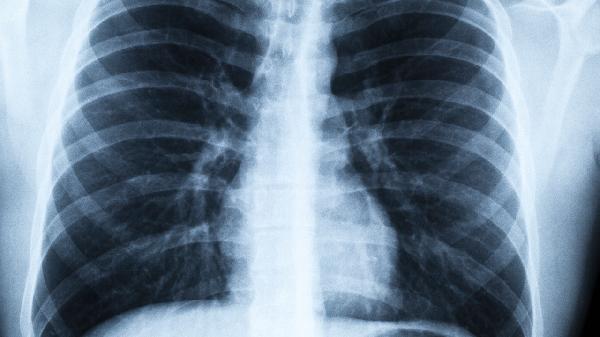

听说体检报告上的"结节"两个字能让人瞬间心跳加速?别慌!肺结节≠肺癌,但有些微妙变化确实值得警惕。今天咱们就聊聊那些藏在CT片里的健康密码,顺便解锁几个让肺部"开心"的日常操作。

1.尺寸悄悄长大:半年内增长超过2mm的实性结节,或磨玻璃结节出现实性成分,就像沉默的哨兵突然举起了警.示牌。

2.边缘长出毛刺:原本光滑的轮廓突然变得像太阳光芒般放射状延伸,这种"张牙舞爪"的形态可能不是好兆头。

3.内部密度改变:磨玻璃结节里冒出实性小点,或者实性结节开始出现空洞,相当于平静湖面突然泛起可疑的涟漪。